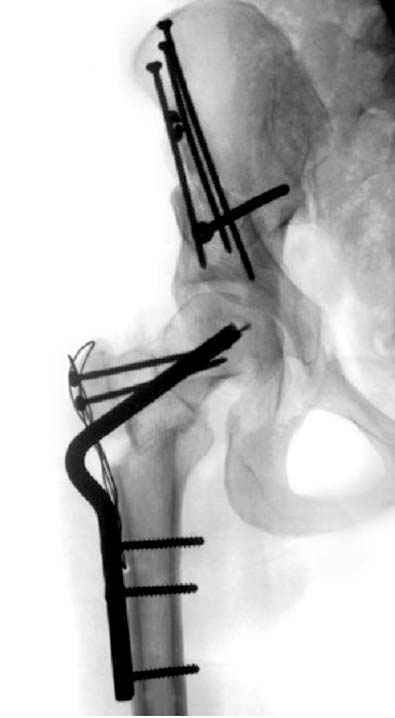

Модель несовершенна, согласен, однако я экспериментировал и с импровизированной илеофеморальной связкой и ацетабулярной губой. Результат был тот же, подвижный узел замыкался посредством аналога СГБ. Для интереса я прилагаю фото., где сымитированы наружные связки и вертлужная губа, но без СГБ видно по показаниям динамометра, что данные структуры незначительно только на 0.5 кг разгружают аналог отводящих мышц. Почему модель получилась именно такой можно рассказать и подробнее если захотите…